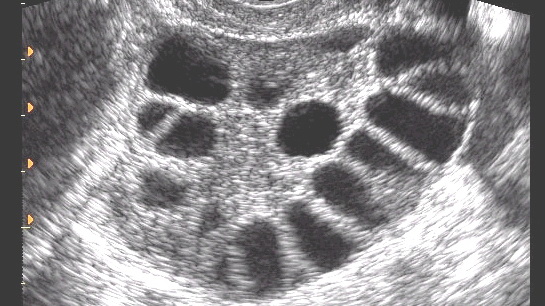

Името полицистични јајници доаѓа од изгледот на јајниците кај некои жени кои го имаат овој синдром – големи или нормални јајници со многу мали цисти. Точната причина за појавата на полицистичните јајници не е позната, но се знае дека овој синдром е една од најчестите причини за неплодност кај жените.

Не постои одреден тест кој можете да го направите и кој да ви даде позитивен или негативен одговор дали го имате овој синдром. Докторот специјалист ја прави дијагнозата откако ќе ги земе во предвид сите симптоми и резултатите од ултразвукот и тестовите на крвта. Со тестовите за крвта се измеруваат нивоата на хормоните, а со ултразвукот може да се видат јајниците и образуваните по нив цисти.